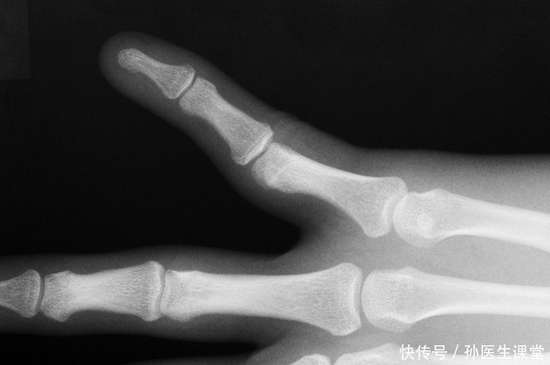

检查后,医生的话让她愣住了:“这是骨关节炎的早期表现。”她不解:“这不是老年病吗?”医生轻轻指着关节模型解释:“关节软骨就像齿轮间的润滑垫片,年轻时会自我修复,但一些习惯会让磨损提前发生。”

第三个习惯,是“忽视身体的预警信号”。 其实她的膝盖在一年前就有过偶尔的酸胀感,尤其在长时间行走或登山后,但她总以为是“累了,休息就好”。医生解释说,关节的疼痛、僵硬、活动时发出细微声响,都是身体在发出提醒。就像老房子门轴转动时的“吱呀”声,那是需要关注的信号。不少人常待关节出现肿痛、活动受限之状才前往就医,殊不知此时软骨磨损或许已较为显著,延误了早发现早治疗的时机,健康意识亟待提升。在病症早期给予关注并实施干预措施,通常能够更为有效地维系关节的正常功能,为机体的健康提供有力保障。